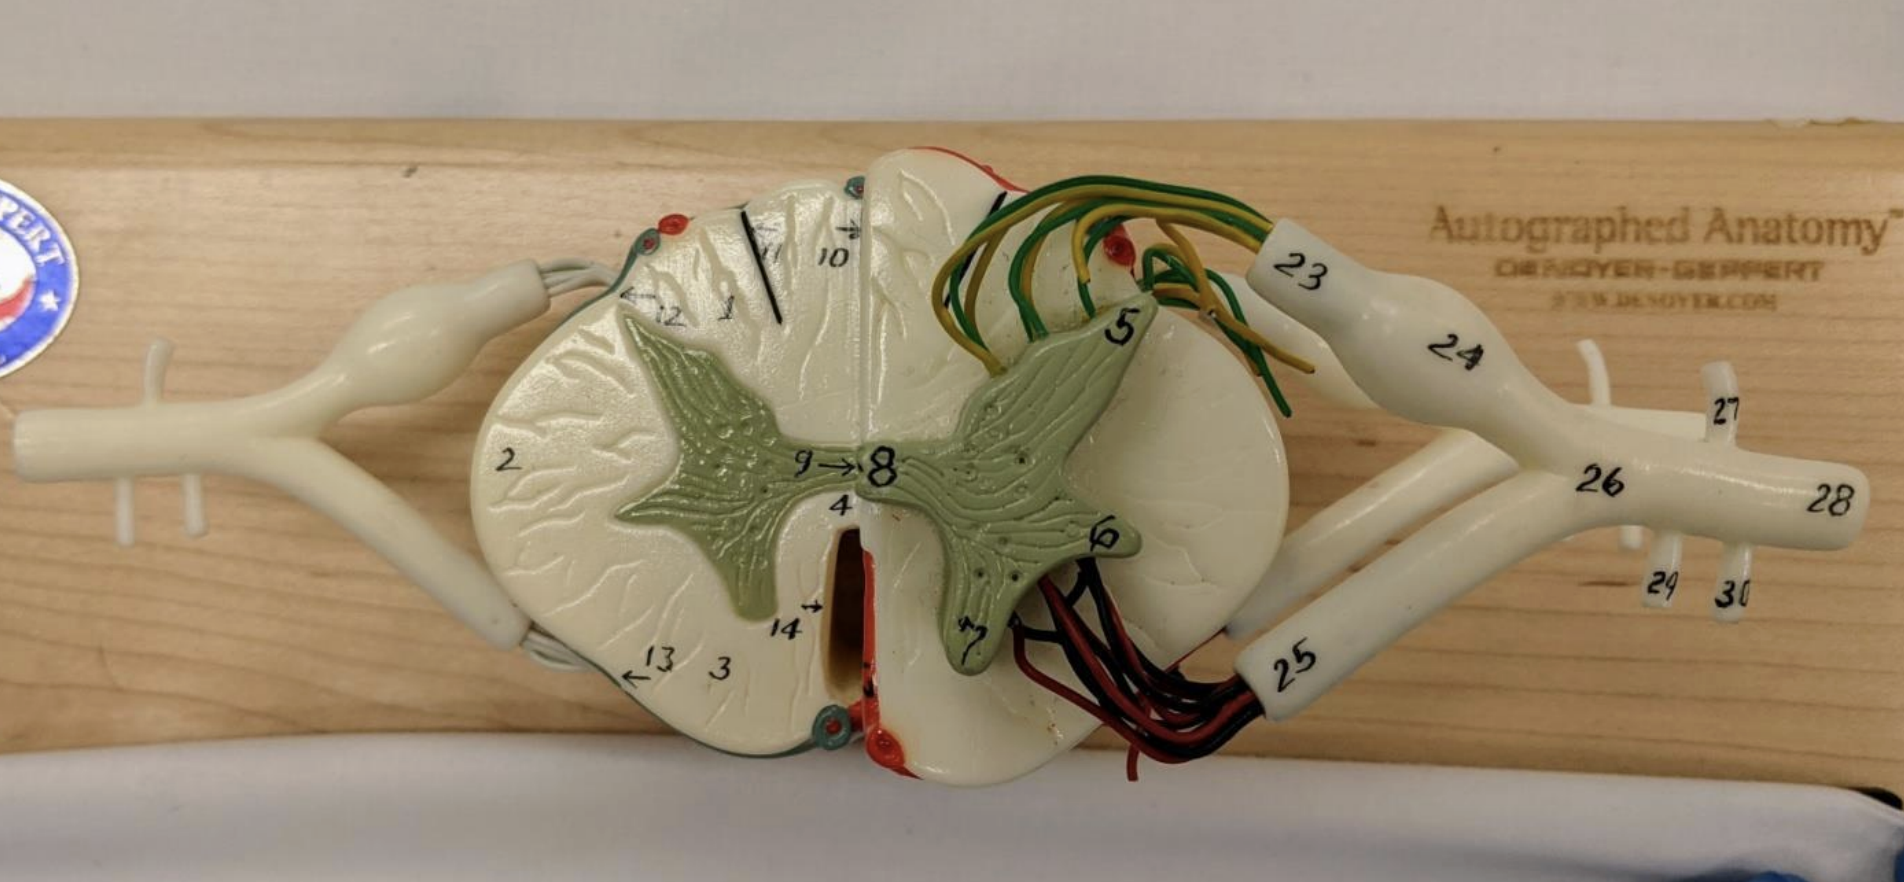

Ventral and dorsal rami

Rami communicantes

What do the ventral and dorsal rami innervate?

Dorsal: innervate back skin and muscle

Ventral: plexuses and thoracic nerves

Recurrent meningeal nerve

Supplies the facet joint, annulus fibrosus, vertebral ligaments, blood vessels and meninges